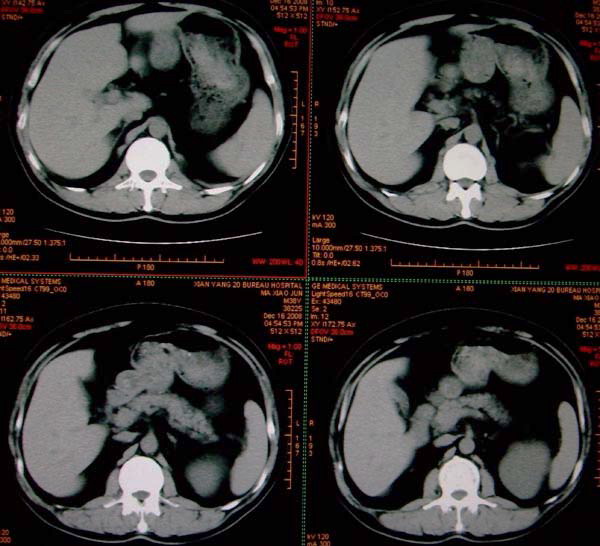

标题: CT17174:M38Y,体检超声提示右肾发育不良,病人无明显不适 [打印本页]

标题: CT17174:M38Y,体检超声提示右肾发育不良,病人无明显不适

右肾发育不良;考虑左肾下极血管平滑肌脂肪瘤可能,建议增强。

1)左肾下极占位性病变,不排除肾癌可能;建议行进一步检查。2)右肾发育不良。

左肾下极占位性病变,不排除肾癌可能;建议增强及明确内部组织ct值。右肾发育不良。

右肾发育不良。左肾代偿。左肾下极占位,性质待定,建议强化。

右肾发育不良。左肾下极囊实性占位,建议增强。